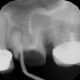

Rentgenowskie zdjęcie będzie także potrzebne czy wręcz niezbędne podczas przygotowań do leczenia kanałowego. Dzięki zdjęciu RTG lekarz będzie w stanie prawidłowo ocenić różne parametry zęba takie jak długość korzenia czy ilość kanałów.

Nasze przykładowe realizacje :